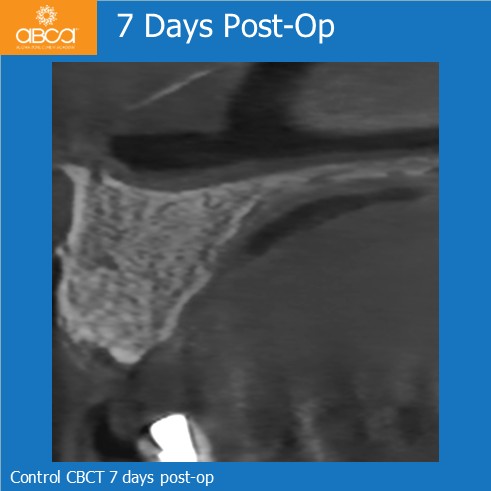

After removing the bridge, Dr. Dudek identified sufficient bone volume at site #12 (7) to place a standard screw implant (Noris Tuff 3.75 × 13 mm). At site #21 (9), only the bone defect remained, with confirmed buccal plate loss. Filling of the defect with 1 cc of Bond Apatite®.

Implant placement at site #21 (9), 5 months post-op. Clinical evaluation demonstrated complete bone regeneration, including restoration of the buccal cortical plate, with excellent revascularization throughout the regenerated site. Histological analysis of a biopsy obtained before implant placement confirmed these findings. In addition, the implant at #21 (9) (Noris Tuff 3.75 × 11.5 mm) achieved excellent primary stability, allowing placement of a healing abutment. After an additional 3 months, the implant site was ready for prosthetic rehabilitation.